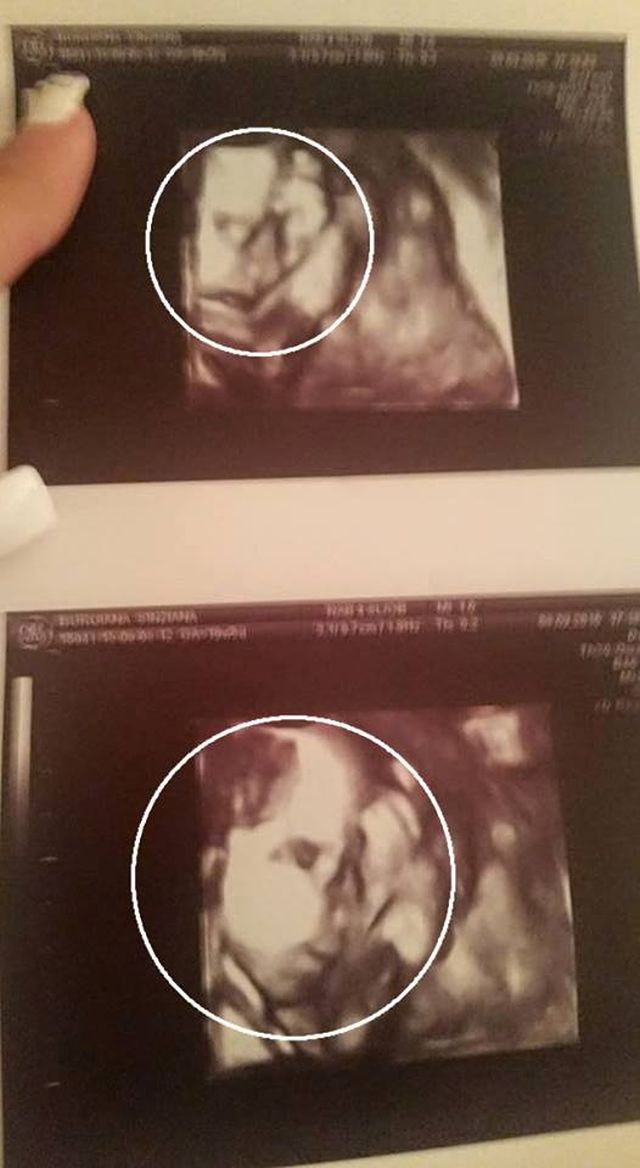

În urmă cu puţin timp, Sânzi a postat pe o reţea de socializare ultima ecografie pe care a făcut-o, în care se poate observa foarte clar faţa fetiţei care urmează să se nască în cel mai scurt timp. "Fetiţa mea frumoasă. Abia aştept să te ţin în braţe", a scris blonda lângă imagine.